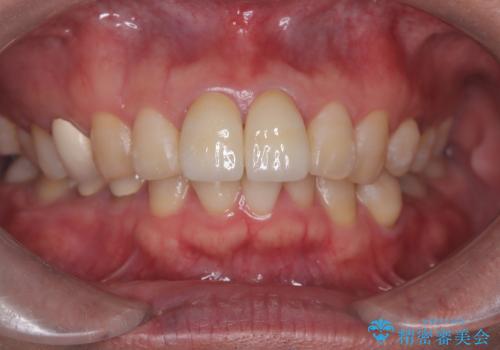

前歯の根のところに違和感がある|根尖性歯周炎|精密根管治療|オールセラミッククラウン|見た目も改善

- 前歯の違和感を主訴にご来院された患者様です。

根尖性歯周炎に罹患し根の先に膿が溜まっているのが原因でした。

精密根管治療後、オールセラミッククラウンで治療を行いました。

治療後、違和感は無くなりました。

治療後、違和感が無くなり、被せ物で歯の長さが揃い見た目も改善されとてもご満足していただけました。